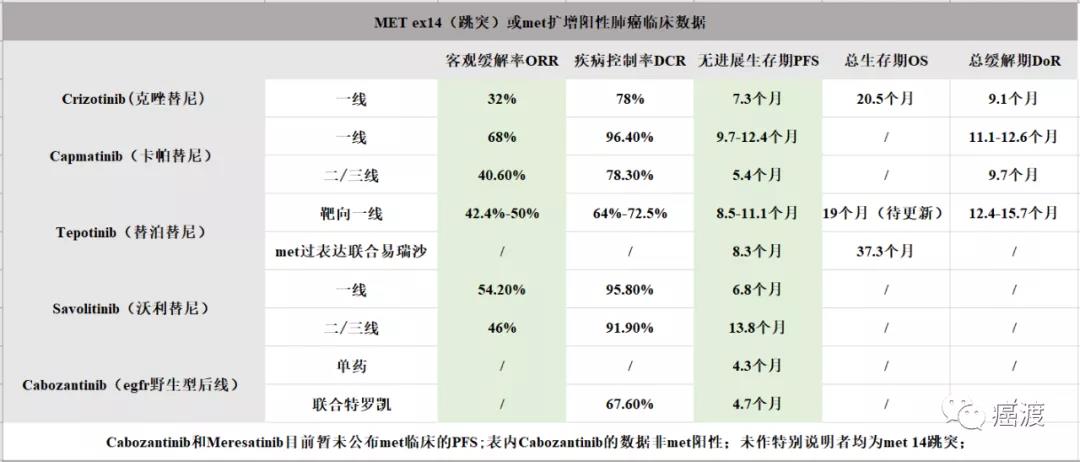

Met突变、扩增和过表达(即met+++,使用met相关药物有效率在66.7%,++、+患者不获益)在肺部原发肿瘤中发生概率不低,它与egfr/alk TKI耐药...